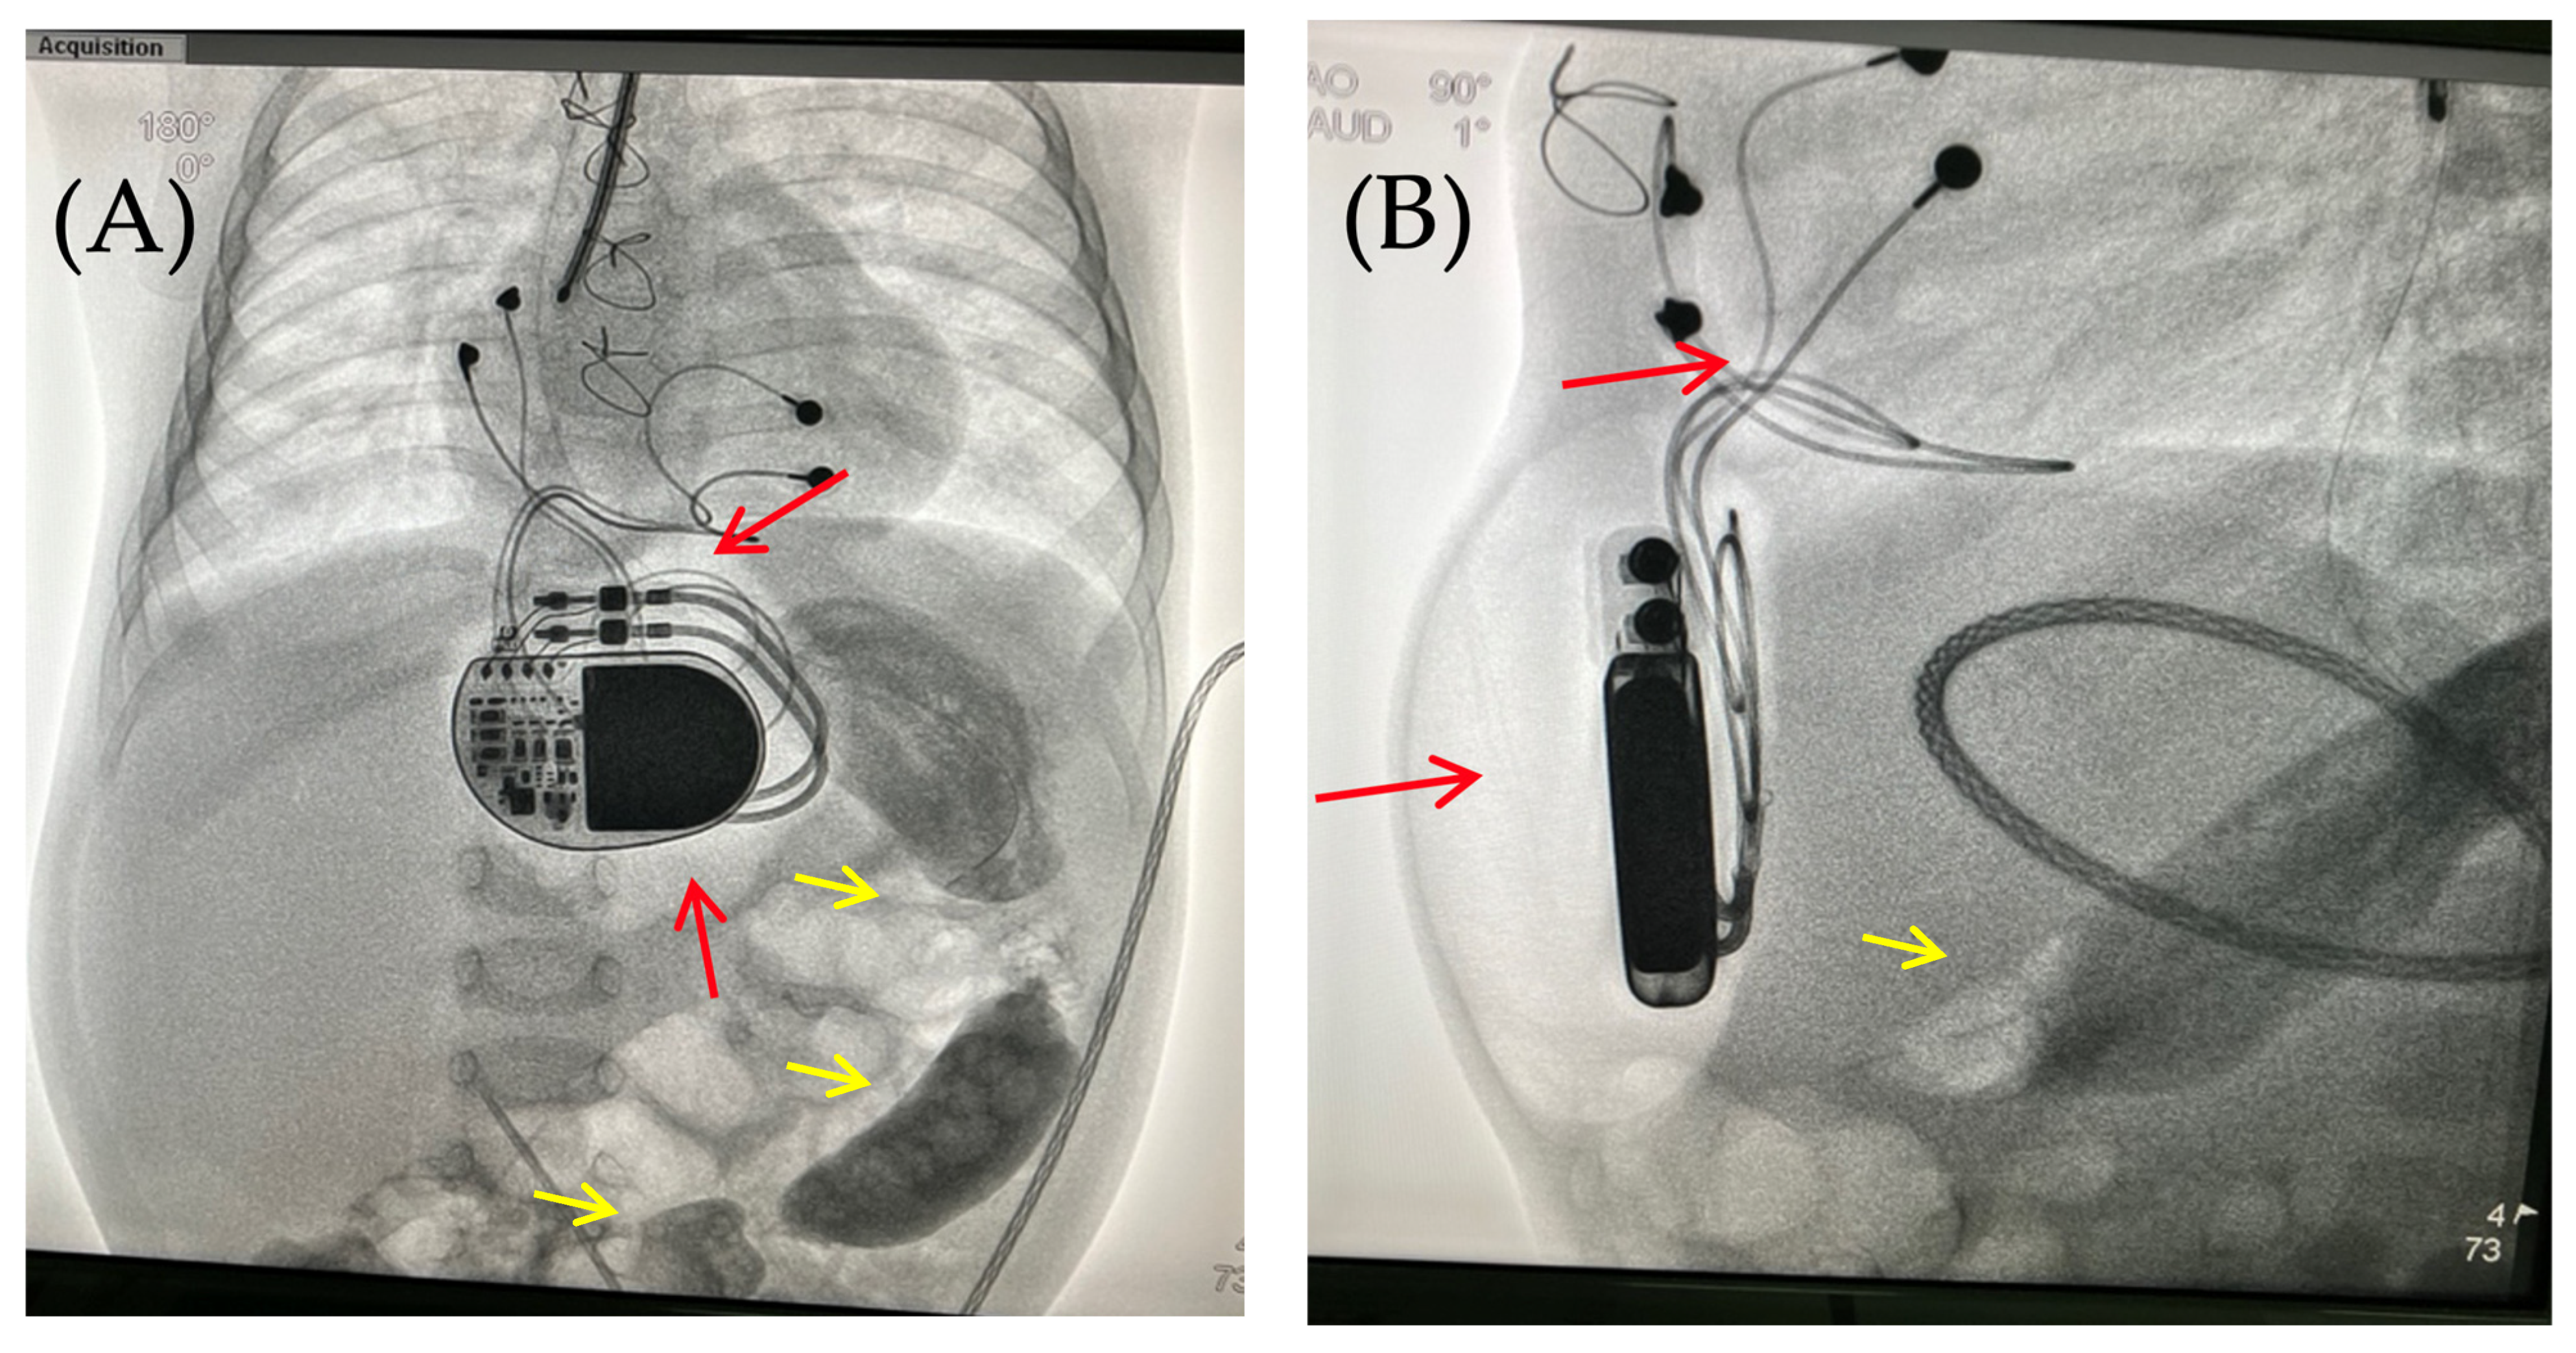

On the 8th postoperative day, the wound healed by primary intention. During pacing programming, impedance values, atrial and ventricular pacing thresholds were satisfactory; no pacing abnormalities were detected. On the 10th postoperative day, local examination in the upper anterior abdominal wall along the midline revealed a localized bulge of skin and soft tissue in the projection of the pacemaker pocket (Figure 1).

Figure 1.

Thoracoabdominal view. Lateral (A) and frontal (B) views. A mass and soft tissue bulge are noted (red arrow) in the area of the pacemaker pocket in the subxiphoid region of the anterior abdominal wall, limited by the projection of the pacemaker body.

The skin in the area of the abdominal wall soft tissue bulge had normal color and temperature. Palpation revealed soft tissue with no detectable fluctuations. The pacemaker pocket was palpated within its bed. To rule out pneumothorax and perforation of a hollow abdominal organ, chest and abdominal radiography and fluoroscopy were performed, as well as GI contrast imaging (Figure 2 and Figure 3).

Intraoperatively, following antiseptic treatment and prior to skin incision, a puncture was performed in the cavity of the pacemaker pocket. The air was evacuated and there was no discharge. Five ml of isotonic saline was administered, the cavity was evacuated, and wound cultures were taken. This was followed by a 5 cm oblique skin incision on the left lateral aspect of the anterior abdominal wall in the subcostal region. The soft tissues were bluntly dissected. The pacemaker pocket was opened. A wound culture was taken. At the revision, the soft tissues were pink and bleeding, with no signs of wound infection. The wound was irrigated with antiseptic solutions. A vacuum drainage system was used (Figure 5).

Figure 5.

Thoracoabdominal view after wound exploration and pacemaker pocket. Frontal view. A dressing with drainage (red arrow) has been placed in the subxiphoid region of the anterior abdominal wall to perform vacuum drainage.